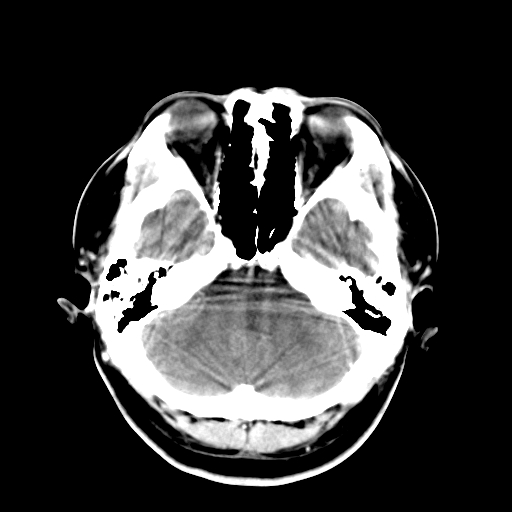

标题: CT16447B:(续)增强扫描图像。

患者今日做ct增强检查,现补传增强扫描图像。

松果体钙癍增大,无其他改变,定不了性

一般认为大于1cm为异常。